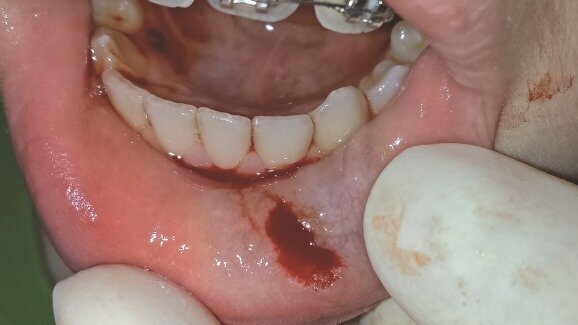

13-letni pacjent zgłosił się do kliniki stomatologicznej z powodu obrzęku wargi dolnej. Zmiana była niebolesna, okrągła, o zmiennej postaci. Jej przyczyną było przypadkowe przygryzienie wargi dolnej 3 miesiące wcześniej. Obecność obrzęku utrudniała pacjentowi mowę oraz żucie. Sprawdzono medyczną i stomatologiczną historię leczenia pacjenta, zbadano go, po czym postawiono rozpoznanie jako mucocela (Ryc.1).

Leczenie polegało na usunięciu zmiany chorobowej za pomocą lasera er:YAG.Podano miejscowe znieczulenie nasiękowe (Ubistesin Forte 1 ml, 3M ESPE). Ustawienia lasera Er:YAG (2940 nm, LiteTouch, Syneron Dental Lasers) były następujące: 200 mJ, 20 Hz, 4 W, czas trwania impulsu <800 µs w trybie do tkanek miękkich, ze sprayem wodnym (poziom 5). Średnica zastosowanej końcówki to 0,6 mm, a długość ¬17 mm, została ona przyłożona do tkanki pod kątem 500. Cała procedura trwała 3-5 min i nie było konieczności zakładania szwów (Ryc. 2). Po usunięciu zmiany nacięcie uciśnięto sterylnym gazikiem oraz przekazano pacjentowi zalecenia pozabiegowe, by unikał kwaśnych pokarmów. Nie zalecono przyjmowania antybiotyków.